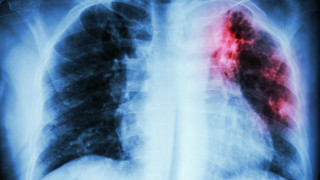

От Здравното министерство призоваха болниците да правят профилактика на туберкулоза

...... лекарска помощ. Наблюдават се големи абсцесни кухини - каверни с т. наречена "букетна инфекция"- на Mycobacteriuum tuberculosis, микотична инфекция и други патогенни бактерии", пояснява специалистът.